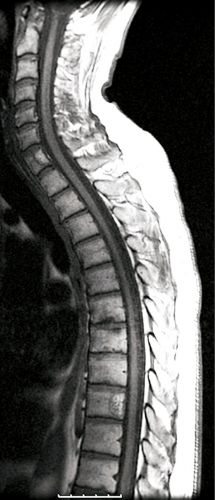

Uppföljning med spinal angiografi ett år senare visade ingen kvarvarande arteriovenös fistel. På MRT 18 månader efter behandlingen sågs inget ryggmärgsödem, och de perimedullära venerna hade tydligt minskat i diameter (Figur 5). Patienten återfick i mellantiden en stor del av sin motoriska funktion och klarade bl a att gå utan rollator. Besvären med urin- respektive avföringsinkontinens förbättrades kraftigt liksom känseln i bägge benen.

Diagnostik. Den kliniska bilden och spinal MRT är helt avgörande för diagnosen. Okunnighet hos kliniker eller radiolog kan få som konsekvens att diagnosen ställs för sent eller inte alls, medan patienten utvecklar en obotlig parapares. De typiska fynden vid MRT är ödem och lätt svullnad av ryggmärgen torakolumbalt samt vidgade blodkärl (vener) dorsalt perimedullärt. Ödemet uppvisar hög signal centralt i ryggmärgen på T2-viktade bilder. De vida perimedullära venerna syns i cerebrospinalvätskan som slingriga strukturer med låg signal på T2-viktade bilder och hög signal på T1-viktade bilder efter intravenös kontrastmedelstillförsel.